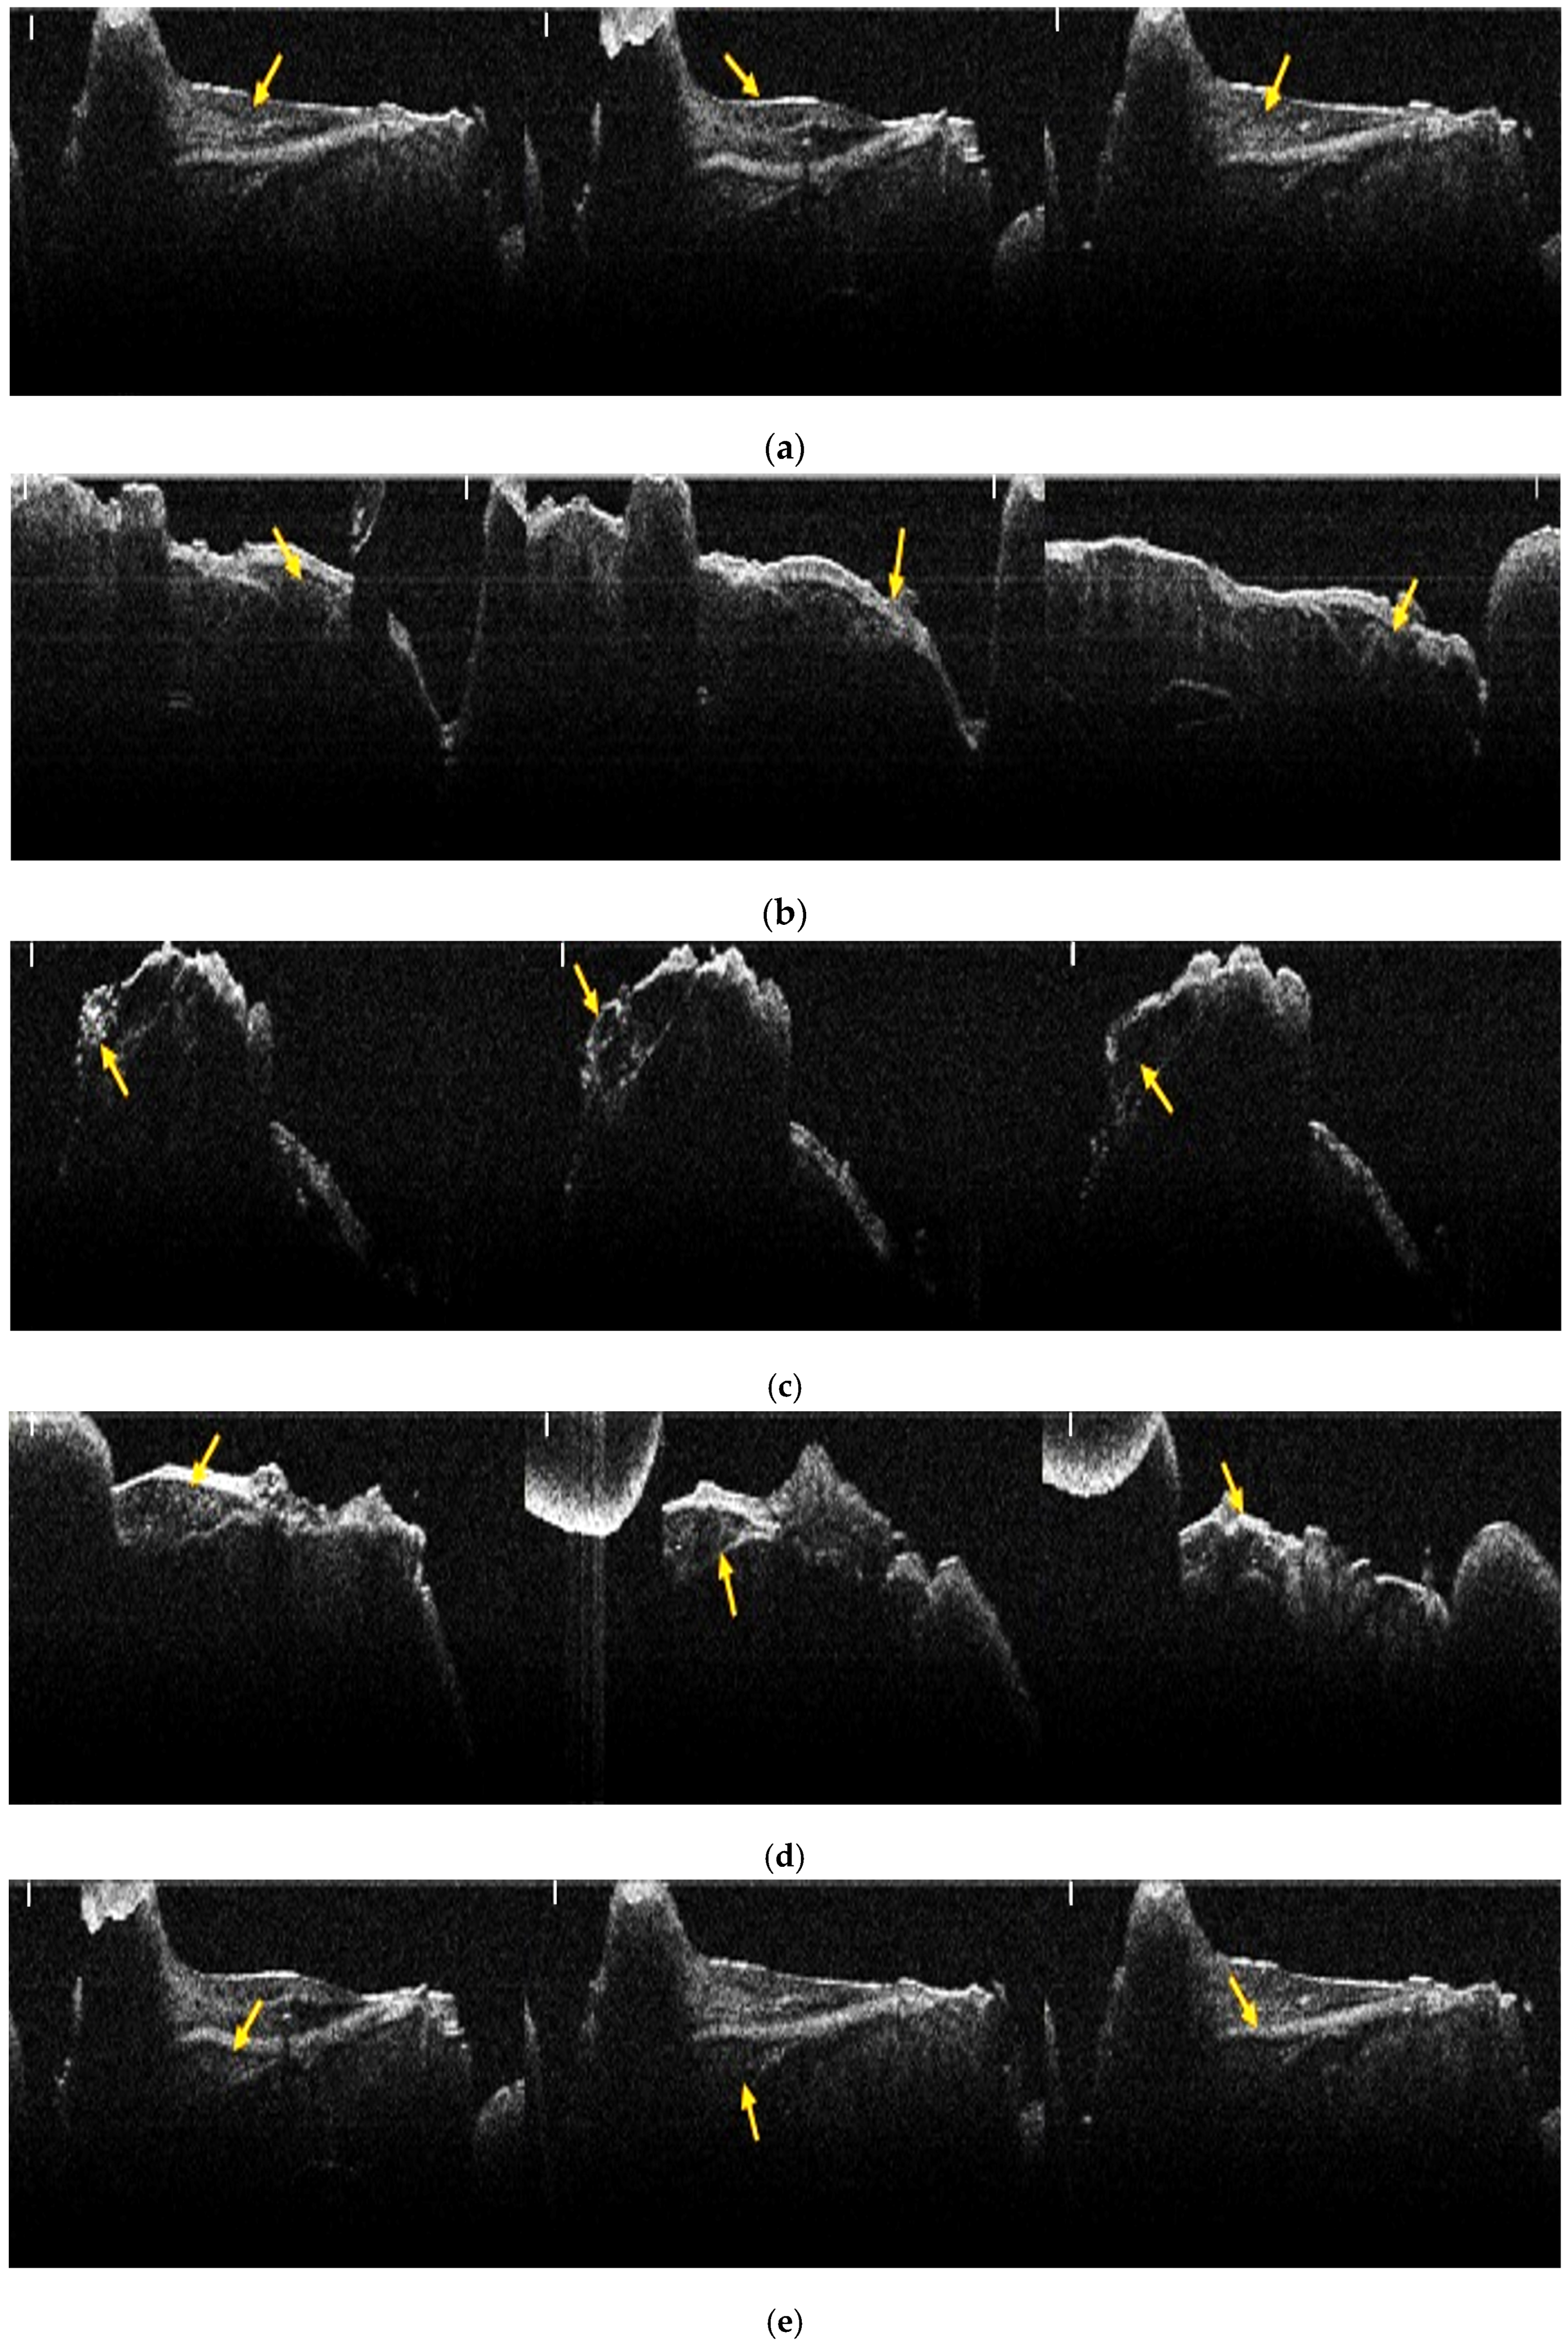

3.1. Results of OCT Analysis of Samples

3.2. Analysis of Bone Evolution Between 2 Months and 4 Months, by Groups and Bone Types